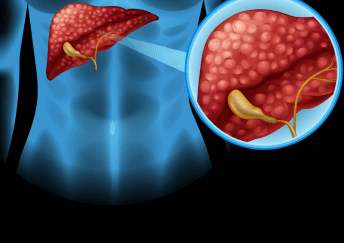

Liver sciences